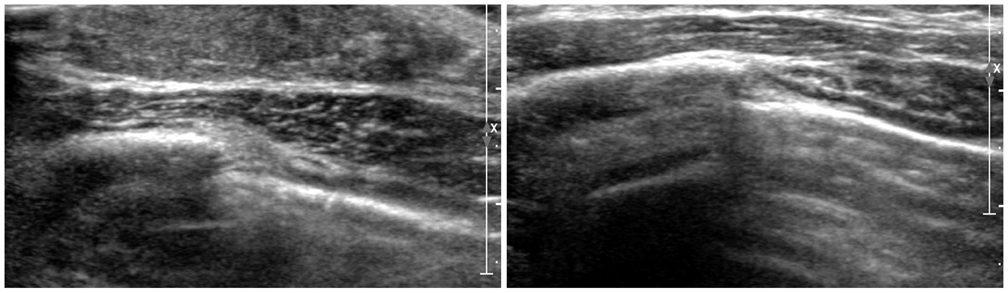

- The purpose of this study is to review various breast diseases in children and adolescents and to illustrate the sonographic findings. We reviewed the cases at our institution in order to identify breast disease in children and adolescent patients who underwent sonography and mammography. Breast disease in children and adolescents included developmental disturbance, infection, benign tumors and inherent defects. In contrast to adults, the radiologic findings of malignant breast conditions in pediatric populations have rarely been reported; however, we show ductal carcinoma in situ with juvenile fibroadenoma and rhabdomyosarcoma. During childhood and adolescence, the recognition and correct identification of physiologic breast development and specific lesions in breast entities on radiologic findings is most helpful in identifying and characterizing abnormalities and in guiding further investigation.